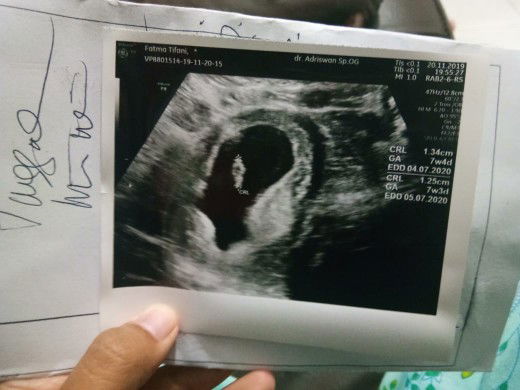

Bun pernahkah selama hamil flek? Awal pertama kedokter ukurang 6 minggu janin belum terlihat Trus diusg 2 minggu lagi janin udah kelihatan dan bagus Lalu diresep kan obat penguat tpi sesudah memakai malalui vagina flek bun Trus 2 hari lagi bali kedokter kata dokternya gpp bun obatnya gak dimasukin ke vagina lagi Tpi diminum 2 kali sehari Tpi kok saya masih tetap flek yg bun Gak sampe di celana dalam Tpi nempeh gitu kuk keputihan Adakah bunda-bunda disini yang mengalamin?